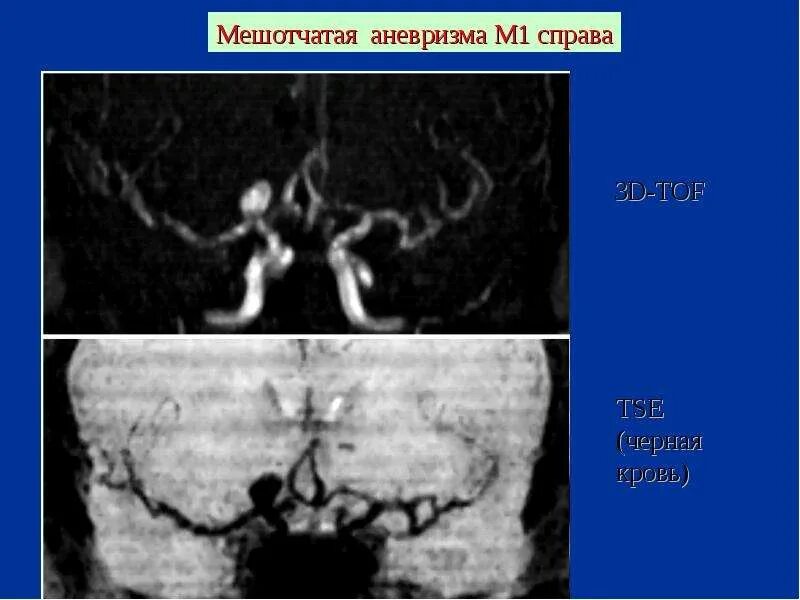

Мешотчатая аневризма внутренней